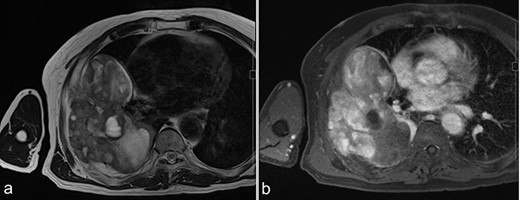

MRI before surgery. (a) T2-weighted MR image shows a mixture of lower and higher intensity areas. (b) An enhanced image shows enhancement in the lower intensity area on T2-weighted images.

A 72-year-old man was referred to our department with a suspected tumor in the right rib. An abnormal shadow in the right chest was found during screening at 50 years of age. The patient was later followed up intermittently by a general physician (Fig. 1a and b). At 72 years of age, he was referred to our department because of a suspected malignant tumor. There were neither subjective symptoms nor abnormal physical findings. A blood test revealed an elevated level for alkaline phosphatase alone at 706 U/L. A pulmonary function test showed a percent vital capacity (%VC) of 78.8%, indicating a mild restrictive impairment. Plain radiography showed a radiopaque tumor measuring 12 × 9 × 18 cm that was connected to the seventh rib in the right thoracic cavity (Fig. 1c). When compared to previous images, the tumor had gradually grown over the preceding 22 years. Computed tomography (CT) showed an extra-osseous tumor-like lesion with calcification, cortical destruction of the right seventh rib and a similar small lesion in the right ninth rib (Fig. 2). Moreover, lesions were also detected in the ninth thoracic vertebral body. Magnetic resonance imaging (MRI) revealed a lower signal intensity inside the lesion compared to the muscle on T1-weighted images and a mixture of low and high intensity on T2-weighted images, while enhancement was observed in the lower intensity area on T2-weighted images (Fig. 3a and b). Bone scintigraphy and positron emission tomography/computed tomography (PET/CT) revealed an increased uptake in the right seventh and ninth ribs and ninth vertebral body, and the right seventh rib showed a high standard uptake value at 7.67 on PET/CT (Fig. 4a and b).